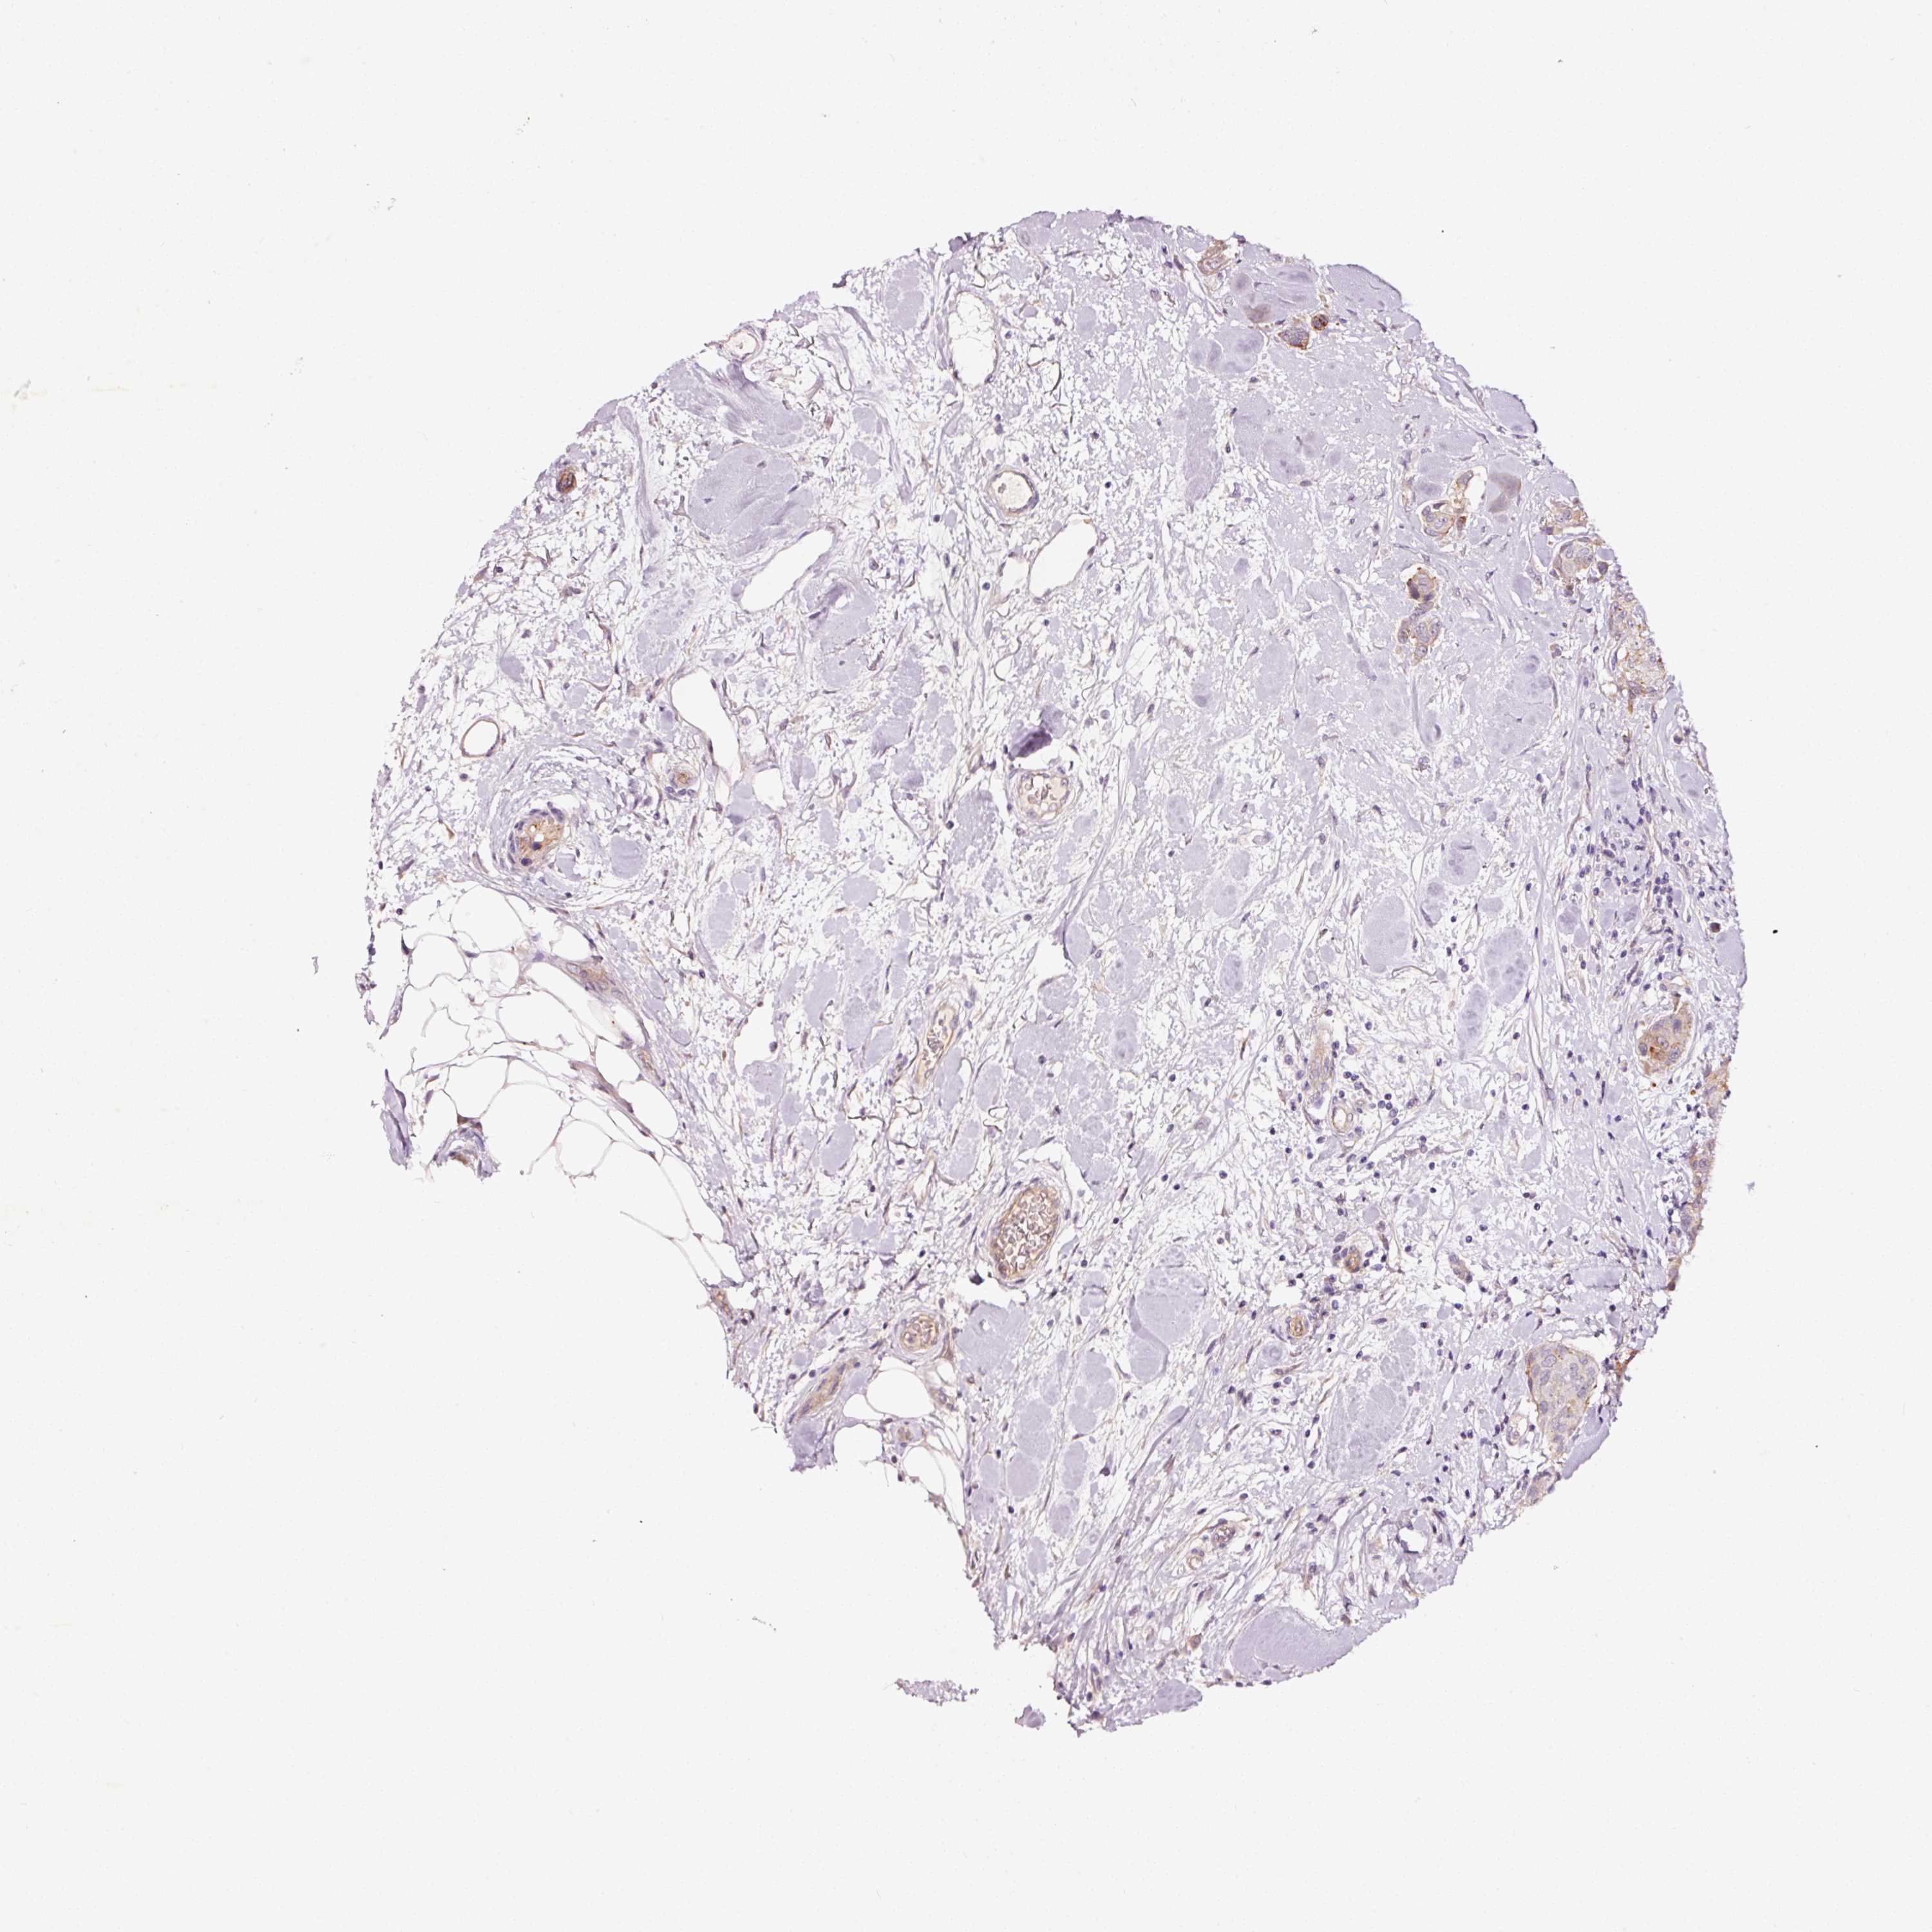

CANCER BREAST CANCER Show tissue menu

BRCA TCGA BRCA VALIDATION PROTEIN EXPRESSION

ANTIBODIES

AND

VALIDATION